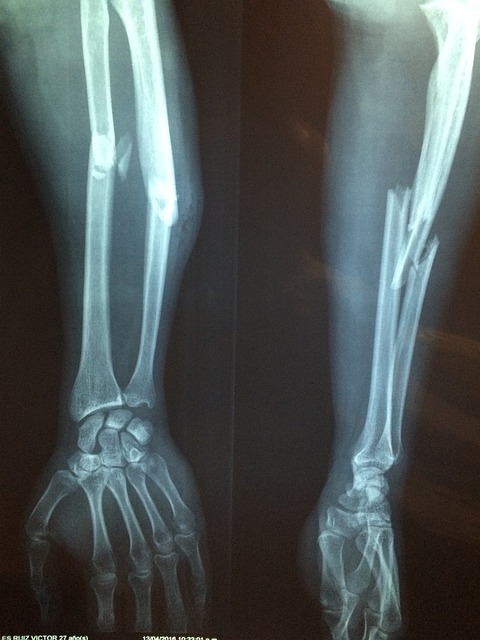

뼈가 부러지면 신체는 이를 복구하기 위해 여러 단계를 거친다. 골절 치유는 크게 네 가지 과정으로 나눌 수 있다: 출혈과 염증 단계, 연골성 가골 형성 단계, 경화성 가골 형성 단계, 그리고 재형성 단계이다.

골절이 발생하면 혈관이 손상되어 출혈이 생기고, 혈액이 응고되면서 혈종(hematoma)이 형성된다. 이 과정에서 면역세포들이 손상 부위로 모여 염증 반응을 일으키고, 손상된 조직을 제거하는 역할을 한다. 또한, 섬유아세포(fibroblast)와 조골세포(osteoblast)가 활성화되어 뼈 재생의 기초를 마련한다. 혈종 형성 후에는 염증 반응을 조절하는 사이토카인이 분비되며, 이로 인해 조골세포의 증식과 분화가 촉진된다.

혈종 내에서는 대식세포(macrophage)가 손상된 세포와 조직 찌꺼기를 제거하며, 이 과정에서 혈관 신생(angiogenesis)이 시작된다. 혈관이 재생되면 골절 부위에 영양과 산소 공급이 증가하여 치유 과정이 가속화된다. 이 단계에서 충분한 영양 섭취와 적절한 혈액순환이 중요한 역할을 한다.

2) 연골성 가골 형성 단계 (1~3주)

손상된 뼈를 연결하기 위해 연골과 콜라겐으로 이루어진 초기 가골(soft callus)이 형성된다. 이 단계에서는 뼈가 아직 단단하지 않으며, 외부의 충격에 취약한 상태이다. 연골 세포들이 점차 증식하면서 뼈 조직으로 전환될 준비를 한다. 섬유아세포와 연골세포가 골절 부위로 이동하여 콜라겐 매트릭스를 형성하며, 이 매트릭스가 골아세포(osteoblast)에 의해 점차 경화된다.

3) 경화성 가골 형성 단계 (3~8주)

연골로 이루어진 가골이 점차 단단한 뼈 조직(hard callus)으로 변환된다. 이 과정에서 조골세포가 활발히 작용하여 새로운 뼈 조직을 형성하고, 석회화가 진행되면서 뼈가 강도를 회복한다. 가골 형성이 진행됨에 따라 골밀도가 점차 증가하며, 뼈 구조가 더욱 강해진다. 이 시기에는 가벼운 활동이 가능하지만, 과도한 하중을 가하면 재골절의 위험이 있다.